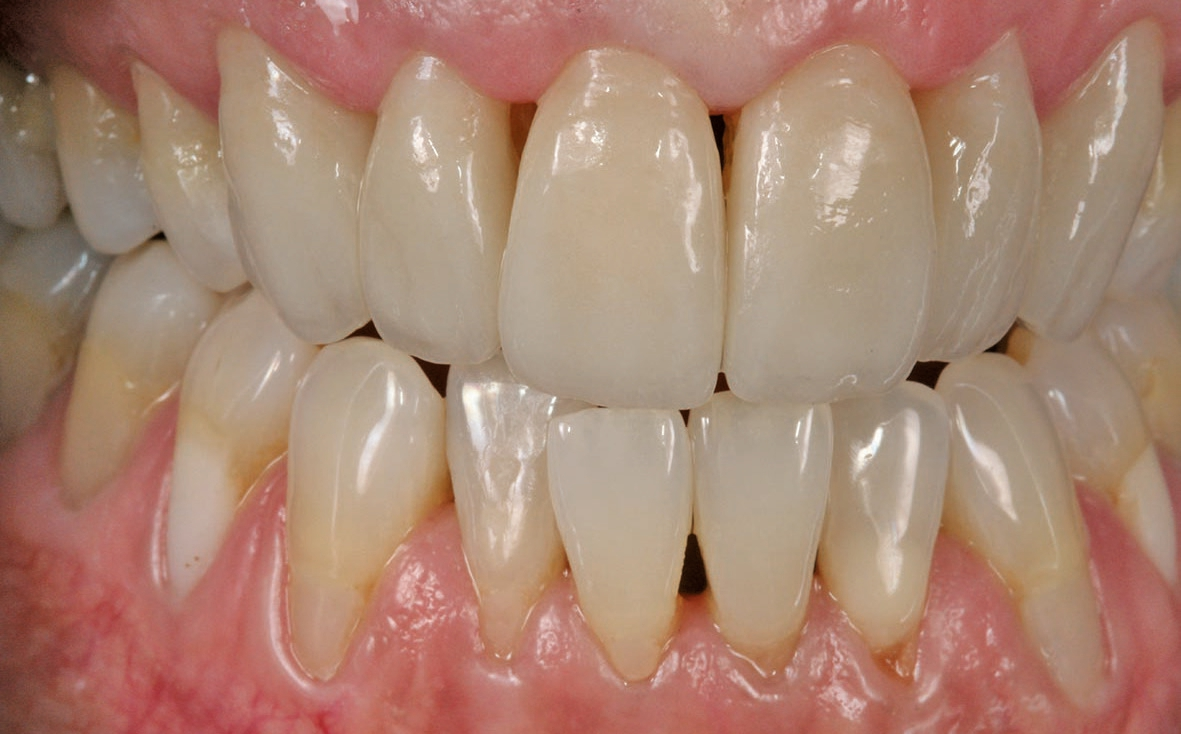

Die fertigen Veneers im Patientenmund

Das Ergebnis hat nicht nur dem Behandler und der Patientin, sondern auch deren privatem Umfeld sehr gut gefallen. Dank der sorgfältigen Analyse, geschickter Materialwahl und eines tollen Behandlungskonzeptes konnten wir die Patientin sehr glücklich machen.